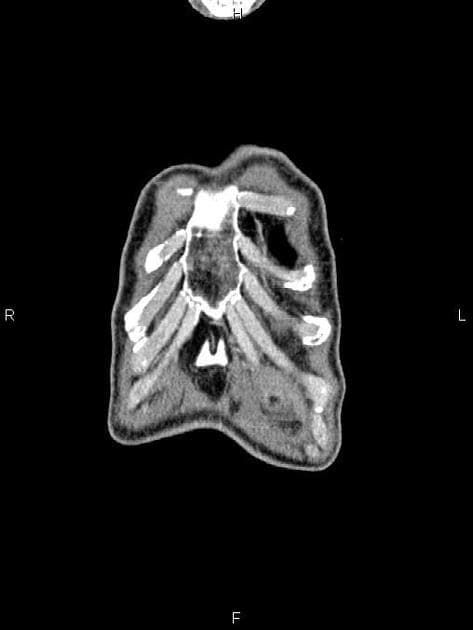

- Dày thành túi mật (gallbladder) rõ rệt, không hạn chế khuếch tán (phù thành không mủ – non-suppurative mural edema)

- Hạch bạch huyết quanh cửa gan (periportal lymphadenopathies)

- Ống mật chủ và ống mật gan trong không giãn

- "Dày thành túi mật là dấu hiệu hình ảnh thường gặp trong viêm gan siêu vi A cấp tính, nguyên nhân do phù thành không mủ."

- "Hạch bạch huyết quanh cửa gan có thể xuất hiện trong viêm gan siêu vi cấp tính và giúp phân biệt với tắc nghẽn đường mật."

Thảo luận